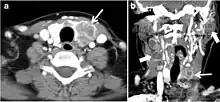

Fig. 10. Metastatic squamous cell carcinoma of unknown origin in a 42-year-old female patient. a, b Axial and coronal enhanced neck CT scan demonstrate infiltrative hypodense left thyroid lobe lesions (white arrows). There are multiple necrotic cervical nodal metastases (white block arrows).[1]